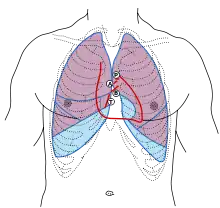

الفحص السريري: أثناء الفحص السريري فإنه يتم الاستماع لأصوات القلب، وهي عادةً ماتمثل انغلاق الصمامات القلبية، الصوت الأول يشير إلى انغلاق الصمامين التاجي وثلاثي الشُرَف، ويعبر عن نهاية دخول الدم إلى بطيني القلب، بينما يمثل الصوت الثاني إغلاق كلا الصمامين (دسامين) الرئوي والأبهري. يُسمع انغلاق الصمام الأبهري في الحيّز الوربي الثاني اليسار كما في الصورة.[5]